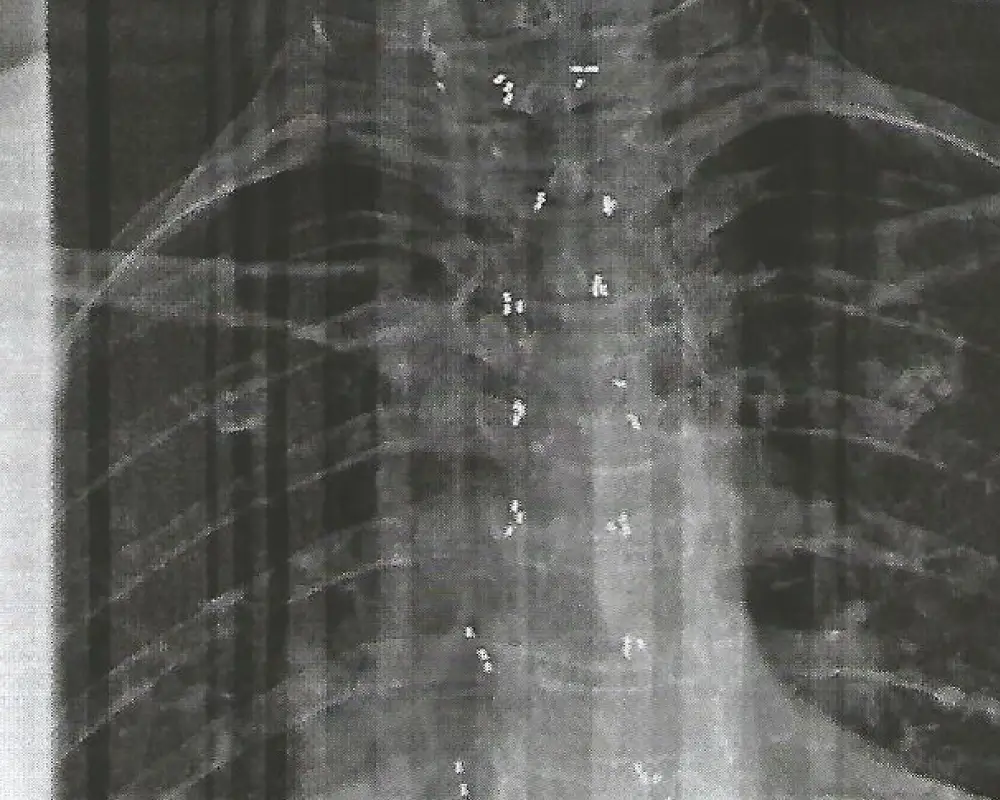

Rücken (Wirbelsäule)

Reduziert Wirbelsäulenbeschwerden und unterstützt die Gewebe­regeneration.

Nach ausführlicher Diagnostik und Beratung werden unter lokaler Betäubung winzige 1–2 mm lange Segmente aus 24-karätigem Golddraht mit einer Hohlnadel rund um das betroffene Gelenk implantiert. Die Goldstücke verbleiben dauerhaft außen an der Gelenkkapsel, wandern nicht und entfalten dort ihre entzündungshemmende Wirkung – ganz ohne Gelenkoperation, Nachoperationen oder Antibiotika­therapie.